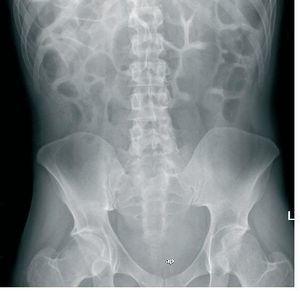

Hombre de 30 años de edad, con antecedentes de encefalopatía connatal y retraso mental secundario, trastorno digestivo connatal, poliquistosis renal crónica con ureterohidronefrosis severa de larga evolución e insuficiencia renal crónica secundaria, con infecciones urinarias de repetición. Dependiente para todas las actividades de la vida. Fue ingresado por un cuadro suboclusivo (figura 1) secundario a cuerpos extraños (plásticos, tierra, etc.), sin datos de laboratorio reseñables salvo creatinina (Cr) sérica de 1,4 mg/dl que ya presentaba en anteriores controles analíticos. Se comenzó desde el momento del ingreso con abundante sueroterapia y enemas de limpieza obteniéndose múltiples tipos de cuerpos extraños durante los 3 días posteriores. Al cuarto día de ingreso inició un deterioro progresivo del estado de conciencia, mostrando en el control analítico de sangre los siguientes parámetros: Cr, 5 mg/dl; urea, 116 mg/dl; Na, 197 mmol/l; K, 2,6 mmol/l; Cl, 159 mmol/l; pH, 7,2; HCO3, 14,9 mmol/l; GAP, 23; Ca, 7,4 mg/dl; P, 14,9 mg/dl, y osmolaridad, 389 mOs/kg. Ante los datos de fallo renal, acidosis metabólica normoclorémica, hipernatremia, hipopotasemia e hiperfosforemia, junto con su grave repercusión clínica, se decidió realizar una sesión de hemodiálisis, con buena respuesta a la misma. Tras dos nuevas sesiones de hemodiálisis se obtuvieron niveles hidroelectrolíticos dentro de la normalidad, con desaparición de la clínica neurológica presentada; en el momento del alta hospitalaria el paciente había una estabilización de las cifras de retención nitrogenada próximas a las de su ingreso.

Figura 1. Rx simple de abdomen al ingreso del paciente.